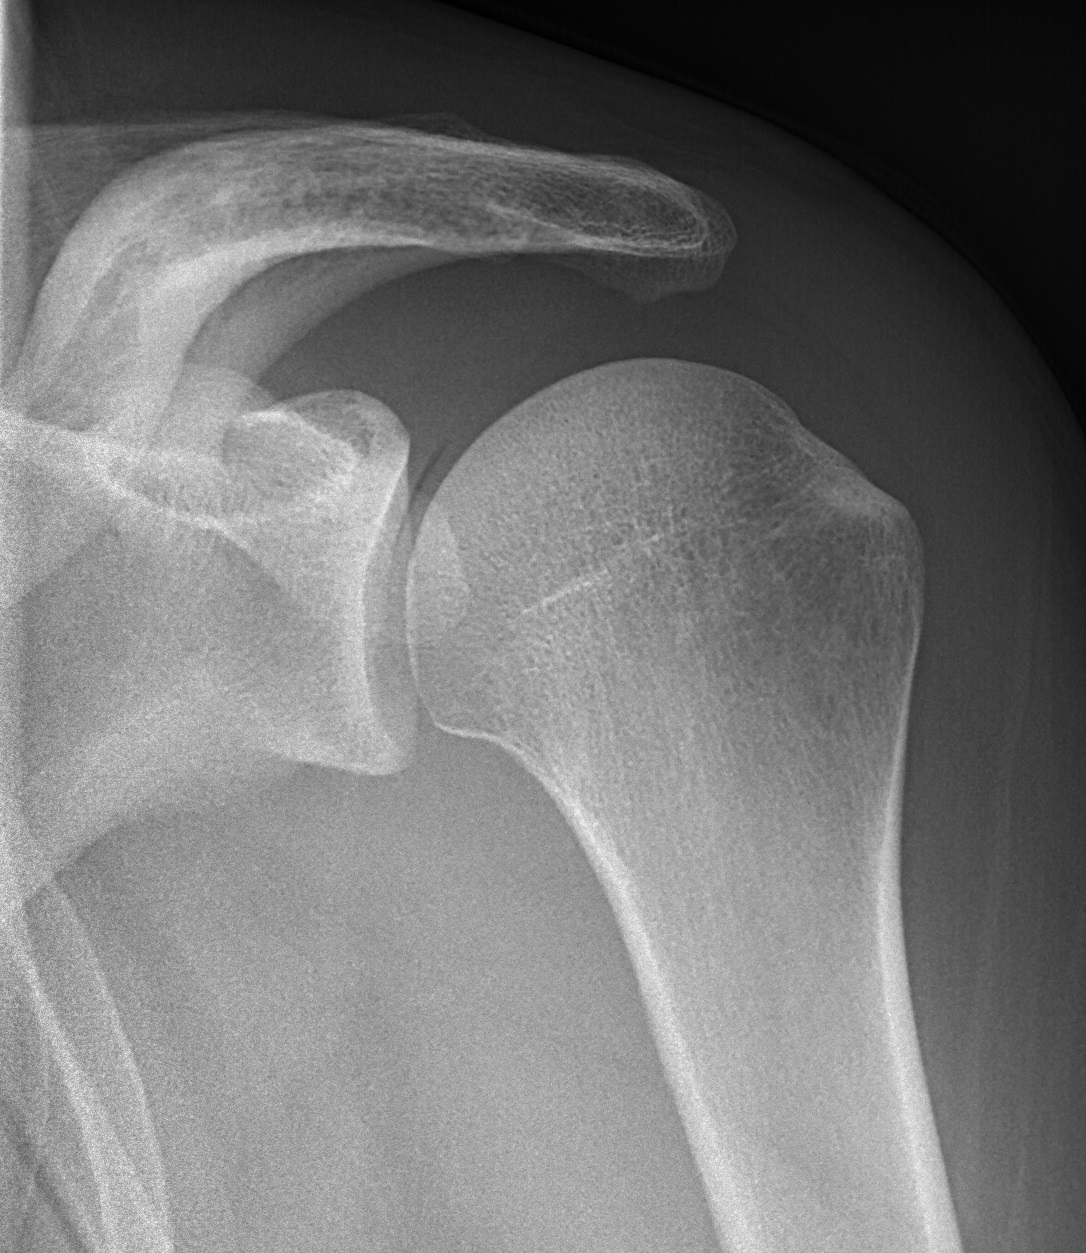

류마티스 관절염은 관절 주위를 둘러싸고 있는 활막이라는 조직의 염증으로 인해 발생하는 질환입니다.

이 질환은 활막이 존재하는 모든 관절, 즉 움직일 수 있는 거의 모든 관절에서 발생할 수 있습니다.